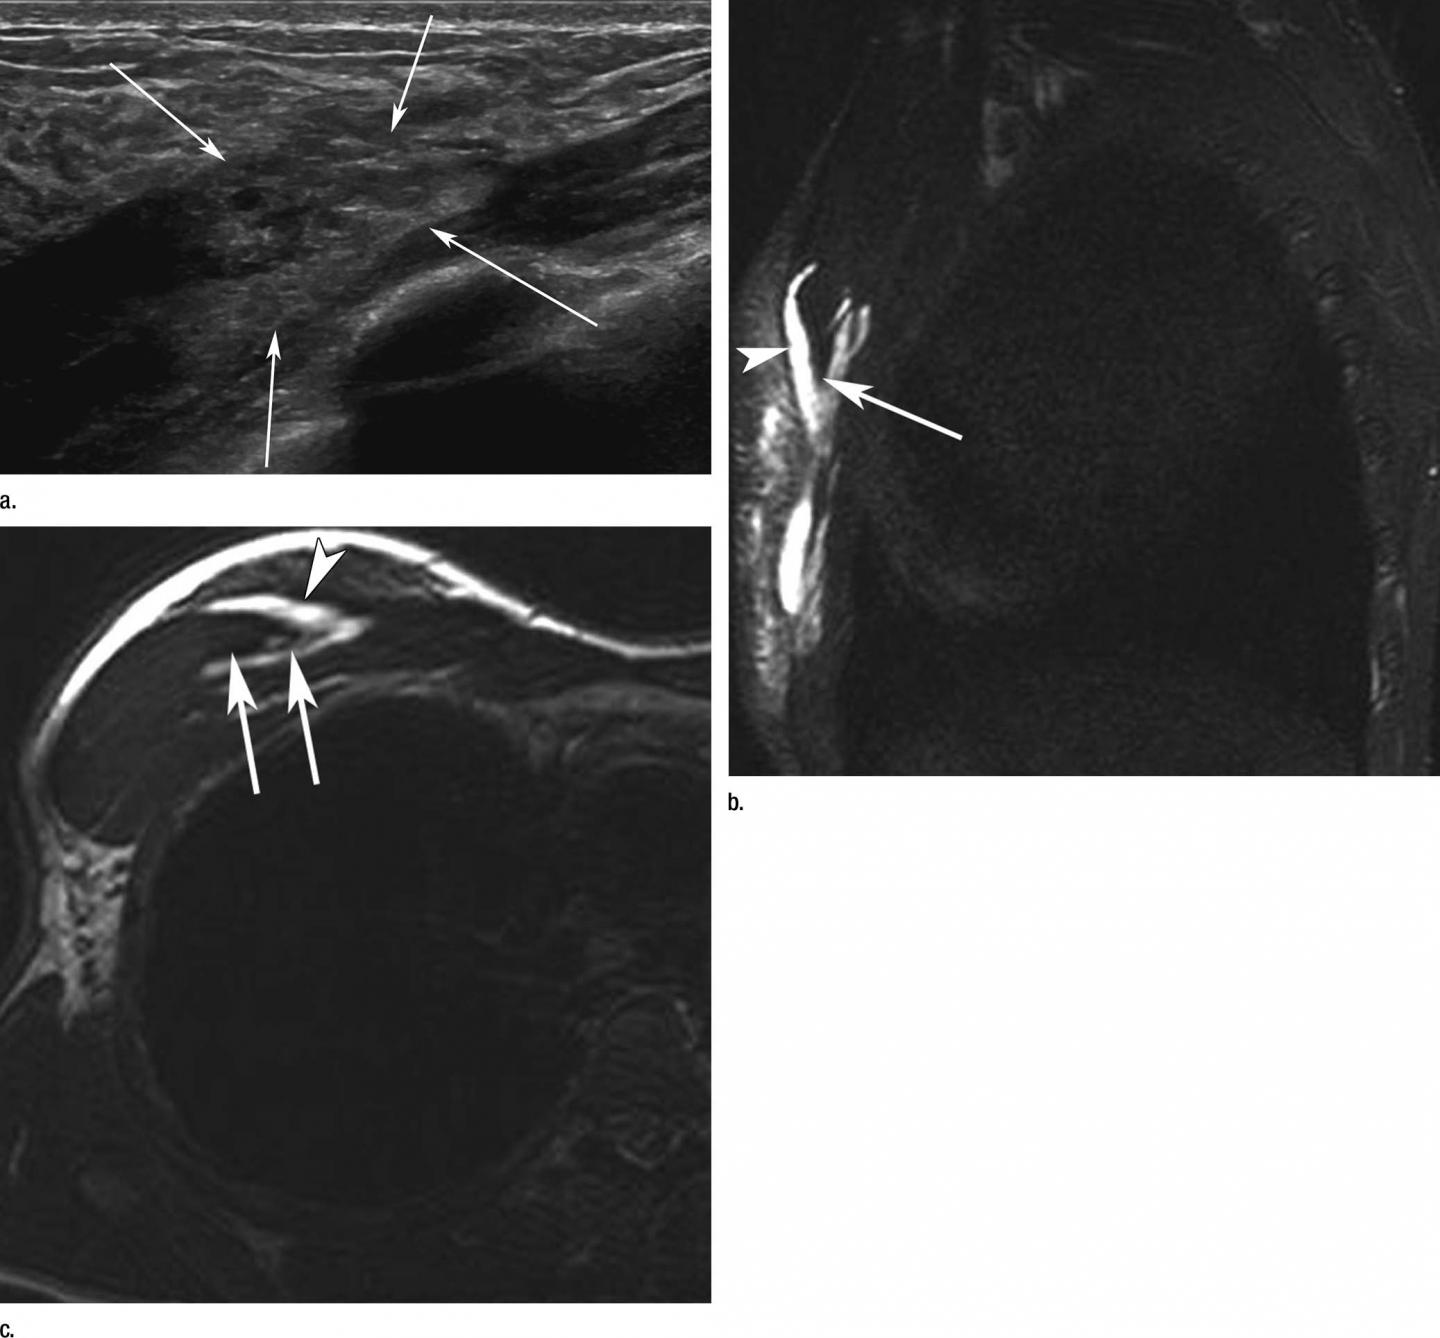

Dr. Guermazi and colleagues set out to describe the occurrence of imaging-depicted sports-related stress injuries, fractures, and muscle and tendon disorders, and to document the usage of imaging with X-ray, ultrasound and MRI.

The lower limb was the most common location of imaging-depicted sports-related injuries overall, and imaging of lower extremities was the most common exam. The second most common location was the upper limb.

Among muscle injuries, 83.9 percent affected muscles from the lower extremities. The sports most prone to muscle injuries were athletics, soccer (football) and weightlifting. Athletics also accounted for 34.6 percent of all tendon injuries.

Eighty-four percent of stress injuries were seen in the lower extremities. Stress injuries were most commonly seen in athletics, volleyball, artistic gymnastics and fencing. Fractures were most commonly found in athletics, hockey and cycling. Nearly half were upper extremity fractures.